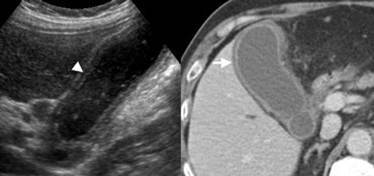

Biliary Obstruction

aka: Double channel

Shot gun

Double barrel

Parallel channel

(dilated biliary duts: A CBD more than 6mm in diameter is considered borderline and more than 10 mm is dilated – will vary by protocol)